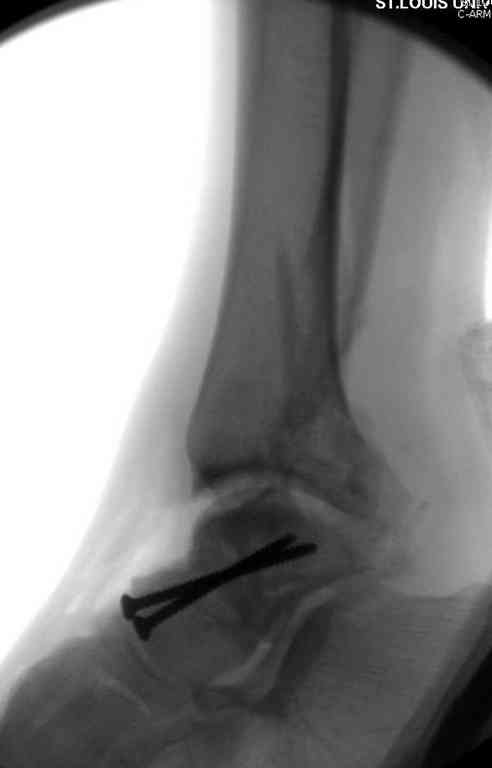

Здесь на фото примеры:

Переломовывих тарана с повреждением медиальной стороны. Через 4 часа после поступления проведена репозиция и фиксация тарана после Irrigation&Debridment. Частичное несращение медиальной лодыжки не беспокоит, вернулся к активному образу жизни. Полная нагрузка разрешена через 11 недель. Финальные снимки через 11 месяцев.